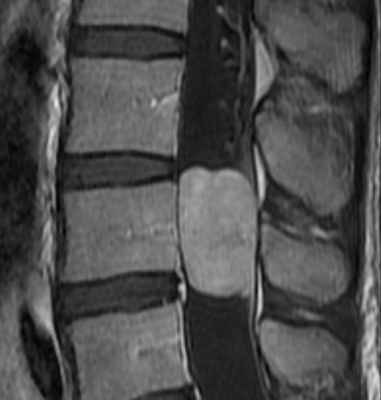

Интрамедуллярные опухоли составляют 10-20% всех интрадуральных образований. У взрослых интрамедуллярную локализацию имеют астроцитома, миксопапиллярная эпендимома, гемангиобластома и метастазы; у детей – пилоцитарная астроцитома, эпендимома, ганглиоглиома.

Астроцитома составляет 30-50% от интрамедуллярных опухолей. Чаще всего спинальная астроцитома относится к доброкачественному пилоцитарному подтипу (G I-II), низкодифференцированная астроцитома и глиобластома встречаются редко. Обычно наблюдается в детском или среднем возрасте без половой предрасположенности. Типичная локализация – верхнегрудной уровень, но может быть астроцитома шейной и шейно-краниальной локализации. Опухоль растет по длиннику спинного мозга, но встречается и экзофитный тип роста. В поперечной плоскости имеет тенденцию к заднему расположению.

При МРТ обнаруживается вздутие спинного мозга, образование изо- или гипоинтенсивное на Т1-взвешенных МРТ, опухолевый узел, отек и киста могут быть одинаково гиперинтенсивны на Т2-взвешенных МРТ. Иногда киста отличается по сигналу от узла в связи с примесью белка или крови. Узел хорошо контрастируется , часто не имеет четких границ и неоднородный (“пятнистый”) по структуре. Реактивные кисты наблюдаются в 30% случаев, они расположены выше и (или) ниже узла и не контрастируются. Некротические внутриопухолевые кисты контрастируются по периферии, причем при визуализации через 20-30 минут могут контрастироваться целиком.